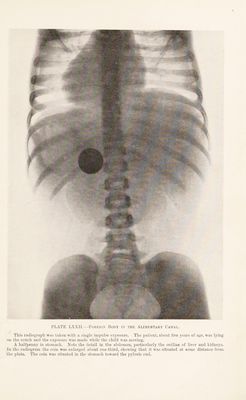

Radiography and radio-therapeutics / by Robert Knox.

- Knox, Robert, 1868-1928